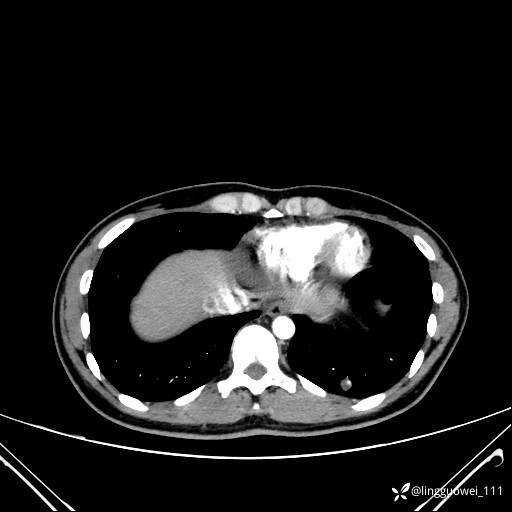

患者性别:女

患者年龄:26岁

主诉:咳嗽来诊,结节性质不明。

肺毛细血管瘤 (2)